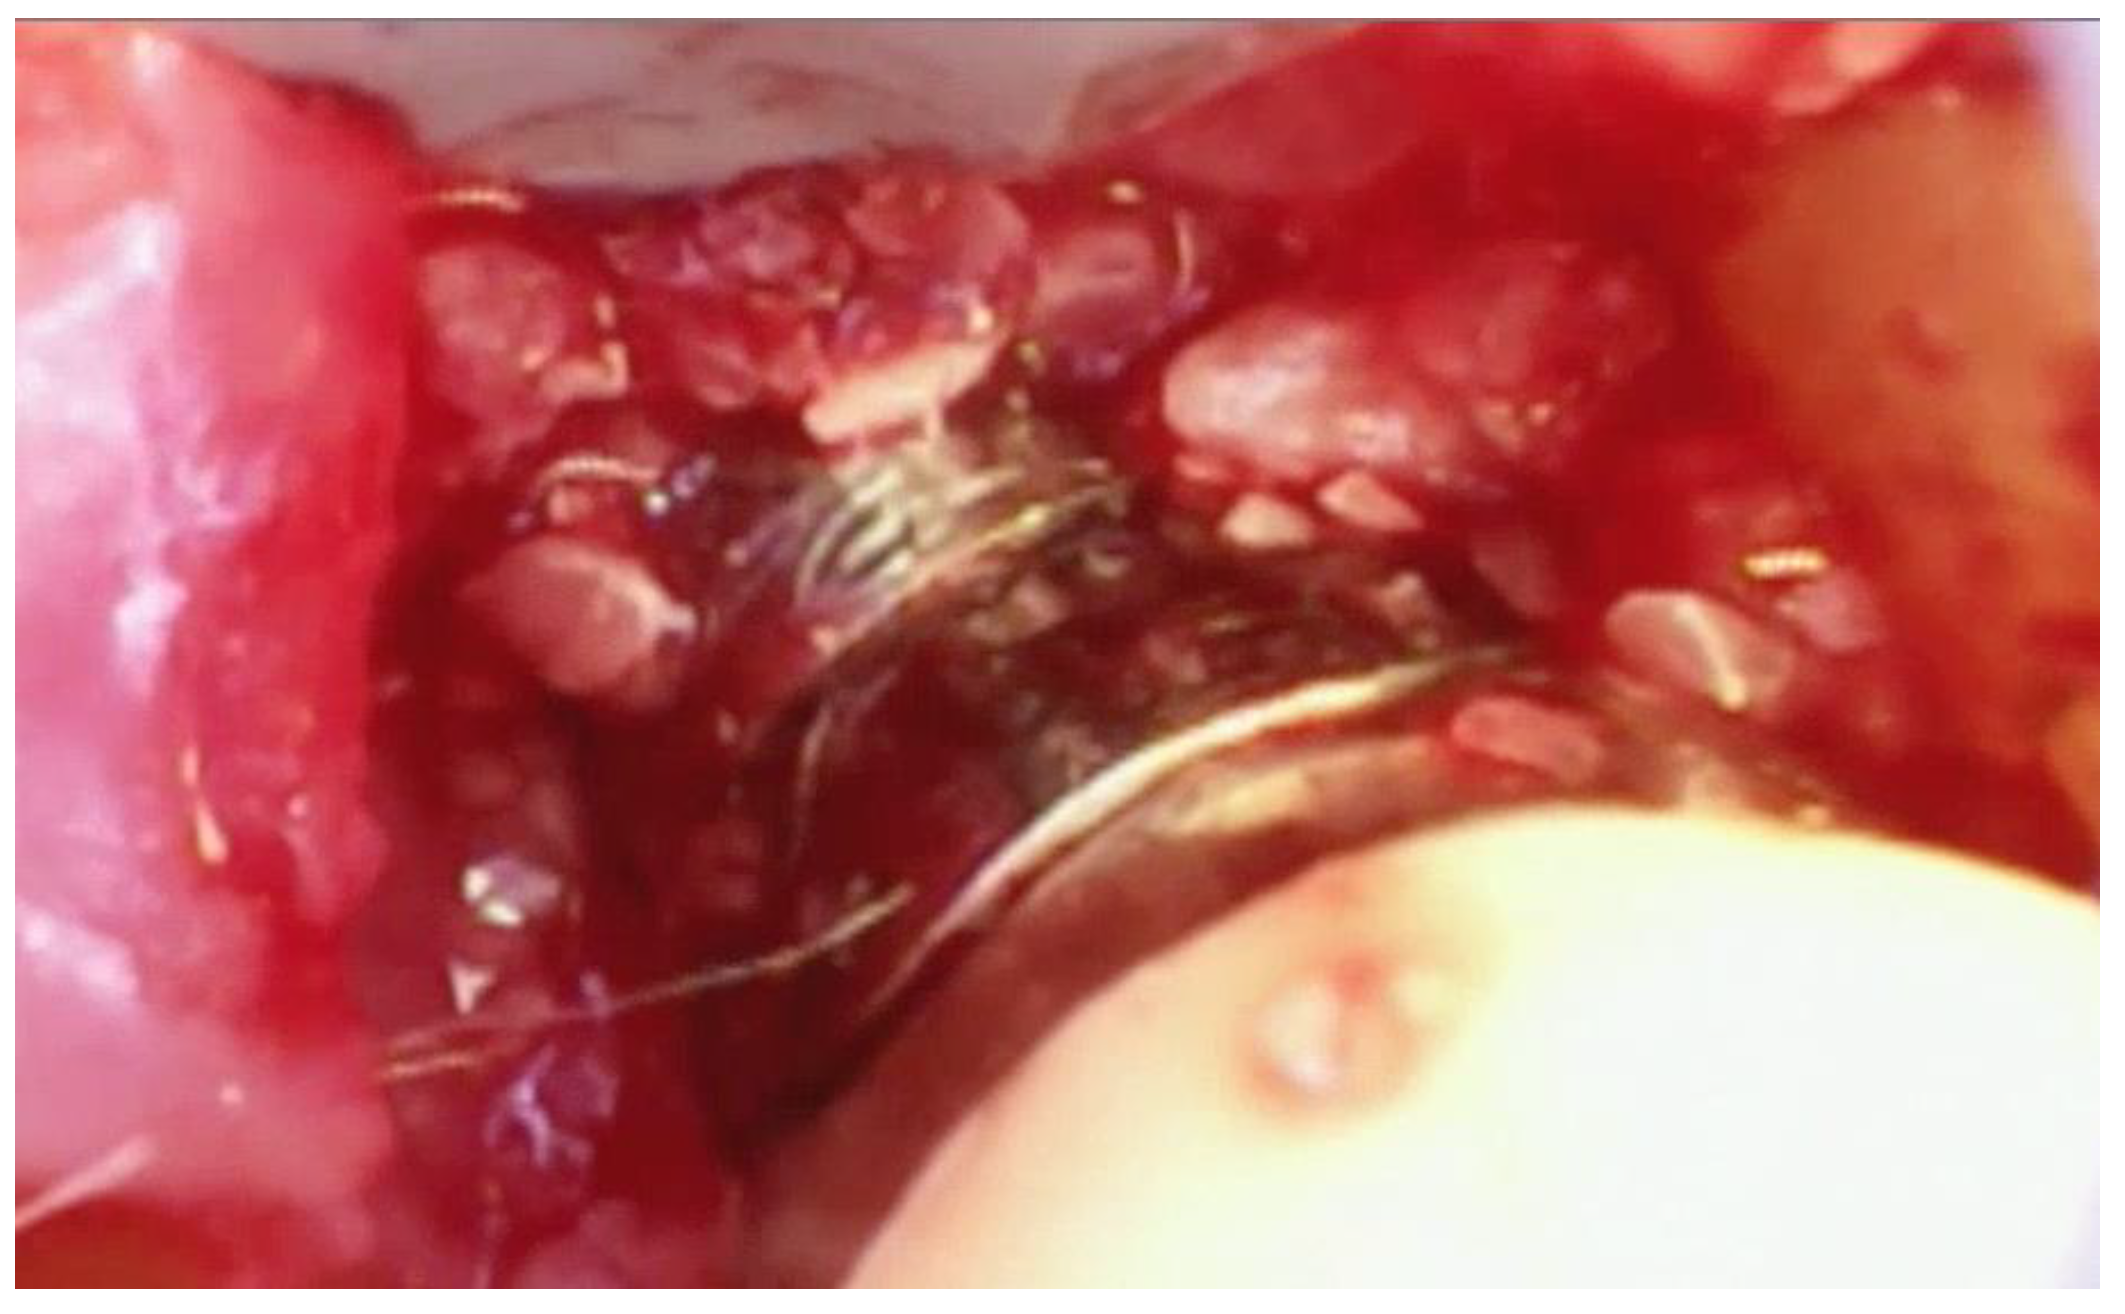

Following the removal of the thin section of tissue, any granulation tissue is removed in a similar manner as performed on natural teeth. However, care should be taken to not touch the implant surface with the instrument used to remove the granulation tissue. The implant surface is covered by titanium oxide, and this has been shown to be an integral part of the osseointegration process [22]. Titanium oxide is very fragile and will be damaged or corroded if the implant surface is touched by an instrument or disinfected with harsh chemicals such as citric acid or a tetracycline solution. Because of this, great care is taken to not touch the implant with a curette while removing the granulation tissue and to only gently wipe the implant surface with sterile gauze soaked in saline. The debrided peri-implant bone loss is shown in Figure 8.

Figure 8. The fully debrided bony lesion can be visualized after removal of the granulation tissue.